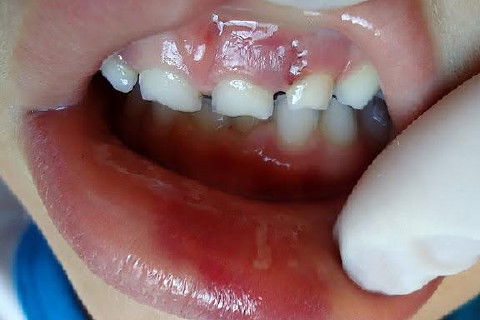

Menino de 6 aninhos sofreu um traumatismo ontem na hora do recreio, lá na escolinha aonde atendo, bateu a boquinha na mesa na hora do lanche.

Examinei-o e constatei ter sofrido apenas uma concussão.

CONCUSSÃO é o trauma dentário menos agressivo que se apresenta.

Sem consequências aparentes ao exame clínico, nenhum dano ao tecido dentário, com pequena agressão aos tecidos de suporte e os dentes apresentam pequena sensibilidade ao toque.

Obs: As duas últimas fotos foram tiradas hoje (24 hs depois).

Fotos do caso